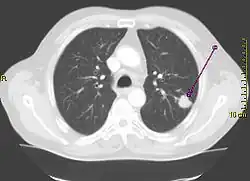

Der Unterschied zwischen der überlagerungsfreien Darstellung in der medizinischen Tomografie und einer Projektionsabbildung ist in den nachfolgenden Abbildungen illustriert. In Projektionsverfahren wie der Radiografie (gewöhnliche Röntgenuntersuchung) wird ein Schattenbild aufgenommen, auf dem sich mehrere Strukturen überlagern, wenn sie im Strahlengang hintereinander liegen. Beispielsweise überlagern beim konventionellen Röntgenbild die Weichteile der vorderen und hinteren Brustwand und die knöchernen Strukturen des Thorax die Lungenstrukturen. Dies würde die Diagnose eines Lungentumors (z. B. Bronchialkarzinom) erschweren. Jedes CT- oder MRT-Schnittbild vom Thorax zeigt dagegen nur eine 0,5 bis 10 mm dicke Schicht, die praktisch überlagerungsfrei ist.

Röntgenbild (Projektionsbild) eines kleinen peripheren Bronchialkarzinoms im linken Oberlappen -

Derselbe Tumor in der Computertomografie (axiales Schnittbild) -

Aus den CT-Einzelschichten zusammengesetztes 3D-Bild